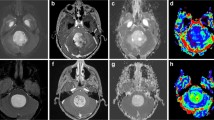

The maximum value of rPH and rPSR, calculated for hemangioblastomas and PAs are shown in Table 2 and Fig. 1. The rPHmax in patients with hemangioblastomas was significantly higher than in those with PAs (5.0 ± 2.7 versus 2.0 ± 0.9, P < 0.001). All lesions in the hemangioblastomas group (100 %) displayed markedly elevated perfusion, while only 9/22 (41 %) PAs showed mildly increased perfusion (rPH > 2.0). From the ROC analysis, with a threshold value of ≥3.2 for rPH, the sensitivity, specificity, and accuracy in the diagnosis of hemangioblastomas were 85.7, 95.5, and 91.7 %, respectively.

Comparison of rPH and rPSR between hemangioblastoma and pilocytic astrocytoma on PWI. b, e Original gray-scale perfusion maps used for positioning of the regions of interest in the tumor. a–c A 44-year-old woman with a solid-cystic hemangioblastomas in the left cerebellar hemisphere. a Axial contrast-enhanced T1-weighted imaging showed intense homogeneous enhancement in the solid portion of the tumor and lack of enhancement of the cystic portion. b, c The red region of interest placed on the enhancing lesion to measure the maximum signal-intensity recovery showed a rapid steep signal drop with a tendency returning to baseline, followed by a second, smaller dip. d–f A 23-year-old man with a solid-cystic pilocytic astrocytomas in the right cerebellar hemisphere. d Axial contrast-enhanced T1-weighted imaging showed intense inhomogeneous enhancement in the solid portion of the tumor. e, f The red region of interest placed on the enhancing tumor to measure the maximum signal-intensity recovery demonstrated the overshooting of the baseline on the recovery maps

In analyzing the percentage of signal intensity recovery, there was a statistically significant difference between the hemangioblastoma group and the PA group as noted in Table 2 and Fig. 1. The signal intensity in 14 PAs cases (14/22, 64 %) exceeded that of the baseline after the first pass, whereas none of hemangioblastoma group exceeded the baseline even at the end of the DSC imaging process. The relative percentage of signal intensity recovery in hemangioblastomas was significantly lower than that in PAs (0.5 ± 0.3 versus 1.0 ± 0.3; P < 0.001). A threshold value of ≤0.9 for rPSR optimized differentiation of hemangioblastomas and PAs with the sensitivity, specificity and accuracy of 85.7 %, 81.8 % and 83.3 %, respectively.